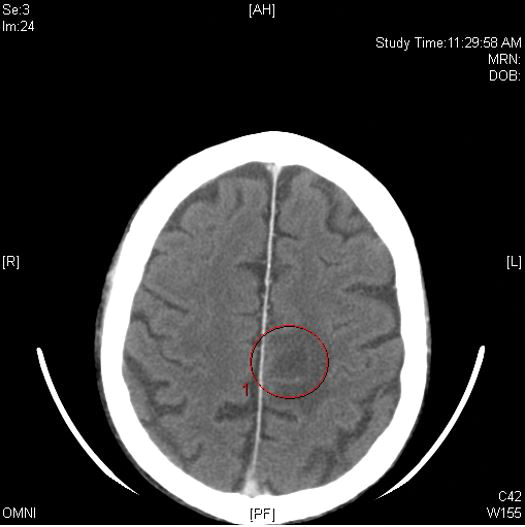

Clinically, the constellation of symptoms was thought to represent an infectious process or less likely metastatic malignancy. Biopsies of the nodule on the right side of the chin were performed and sent for culture and histologic examination. Sections from the anterior right chin showed compact orthokeratosis overlying a slightly spongiotic epidermis (Figure 3). Within the deep dermis, there was a dense mixed inflammatory infiltrate comprising predominantly neutrophils, with occasional eosinophils, lymphocytes, and histiocytes (Figure 4).

Figure 3. Histopathology revealed compact orthokeratosis overlying a slightly spongiotic epidermis with a mixed inflammatory infiltrate (H&E, original magnification ×4).